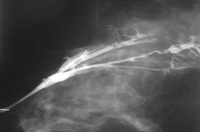

Ductograma en el que se observan múltiples papilomas intraductales

Cortesía de la Dra. Nancy Pile, University of Louisville; utilizada con autorización

Ver esta imagen en el contexto de la/s siguiente/s sección/es: